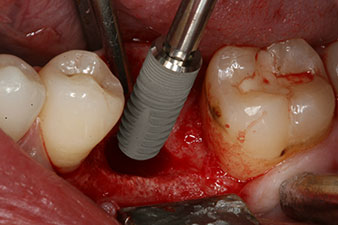

Implantat

Fig. 3: After preparation with the Implantmed implantology motor, an implant (diameter 4 mm, length 12 mm) was screwed in by the motor at a torque of 43 Ncm.

The implant was placed as planned after thorough removal of the granulation tissue (blueSky, bredent).

peri-implant bone deficit

Fig. 5: The peri-implant bone deficit must be compensated with autogenous bone chips to restore the peri-implant tissue contour.

These values could have indicated open healing or even immediate restoration. Due to the insufficient crestal bone volume at the implant, the region was augmented with the bone chips collected during preparation of the implant bed and sutured to exclude saliva.